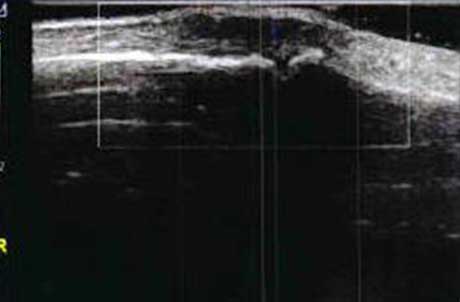

3、准确判断关节积液增加,精准判定RA严重程度

类风湿关节滑膜炎症会导致滑液渗出不断增多,形成关节腔积液。肌骨超声 少可发现1ml的积液,能对关节腔积液量及位置准确定位,通过检测判定关节腔内液性边界清楚的无回声区、细点状回声或细微的低回声条纹,判断其宽度和深度衡量积液量的多少,进而评估RA的严重程度。

Ⅰ级微量积液

滑膜囊内见前后径3.55mm液性暗区,呈椭圆形